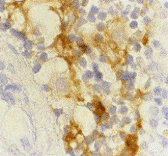

Below: Immunohistochemistry of DC-SIGN in lymph node tissue with DC-SIGN antibody at 10 µg/ml.